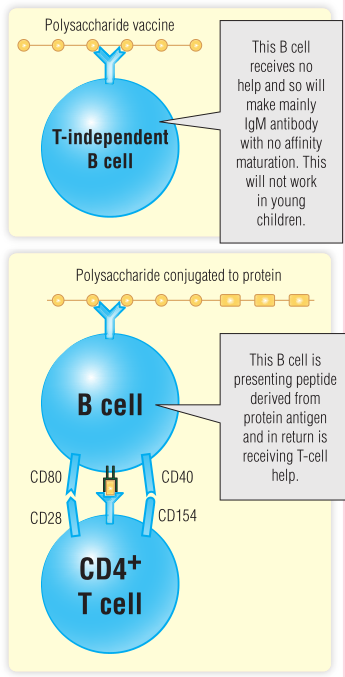

在使用结合疫苗的全国疫苗接种出现之前,由细菌病原体流感嗜血杆菌B(HIB)引起的脑膜炎是一个严重的问题。这种疾病在10-11个月的婴儿中患病率极高,直到18-24个月时,儿童才能产生有效的胸腺非依赖性反应,这是抵御细菌病原体所必需的。严重情况下,缺氧缺血性脑病可能导致神经损伤甚至死亡。最初的疫苗是一种纯化的荚膜多糖,这是一种胸腺非依赖性抗原,在小于20个月的婴儿中不能很好地发挥作用。此外,胸腺非依赖性B细胞不会形成免疫记忆,在免疫球蛋白类别转换或亲和力成熟方面也不起作用。借助对胸腺依赖的免疫反应和B细胞-T细胞在免疫反应中的协作的了解,为一种疫苗的开发提供了思路,在这种疫苗中,细菌多糖与一种蛋白质共价偶联。这种结合疫苗比非结合疫苗产生的反应要好得多,即使在非常年幼的儿童中也是如此。有几种蛋白质用于结合物,包括破伤风疫苗的蛋白质成分。在使用这种结合嗜血杆菌疫苗的国家,脑膜炎发病率已大幅下降。自1993年以来,HIB介导的脑膜炎在美国5岁以下儿童中的发病率下降了95%。

疫苗针对细菌荚膜多糖成分的免疫球蛋白受体的B细胞通过受体介导的内吞作用来吸收结合物。结合物的蛋白质成分可以被加工,并呈现在与MHC II类分子相关的B细胞表面。然后,MHC II类疫苗肽复合物可以被具有适当特异性的T辅助细胞识别,辅助性T细胞激活B细胞,产生针对细菌多糖的抗体。一般原理如Fig16.10所示

Fig 16.10 糖缀合物疫苗的B细胞加工。IgM,免疫球蛋白M。